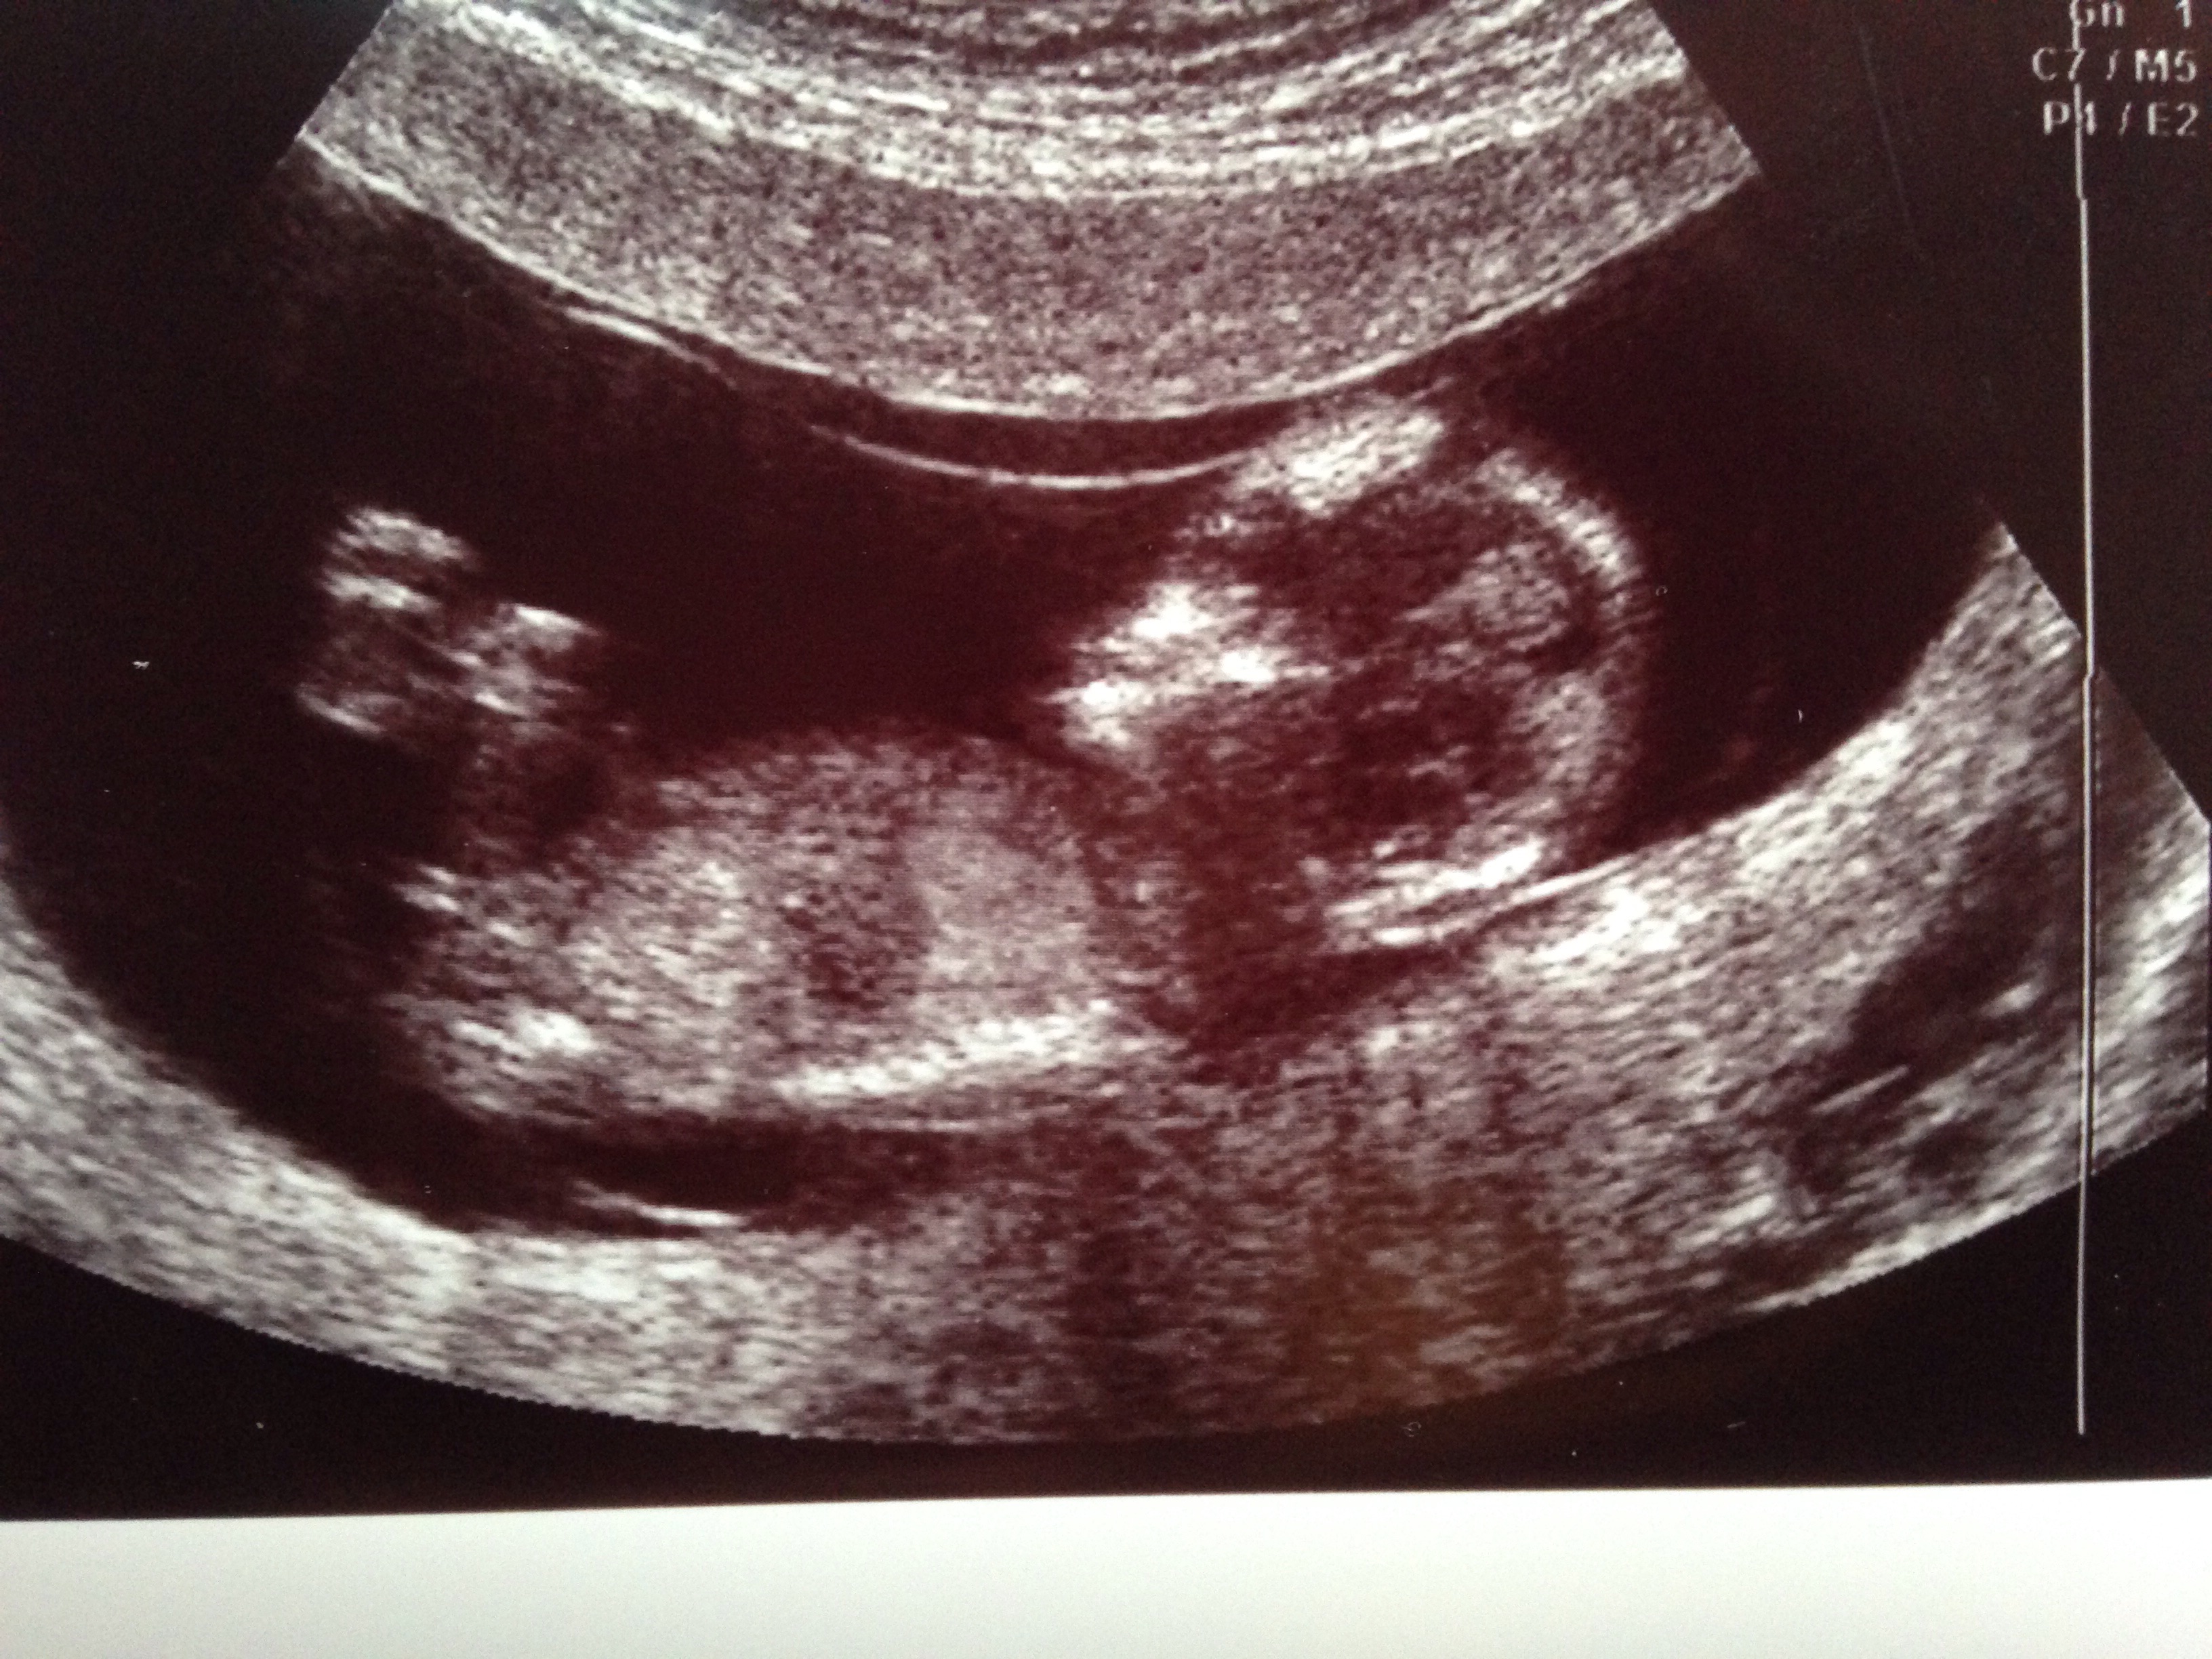

gestation is 13wks - please tell me what you all think?

I would guess boy too; the angle isn't particularly great however the nub is very obvious for 13 weeks. Good luck to her! :) xx

I thought girl from first nub pic. But last nub pic looks more angled up- boyish